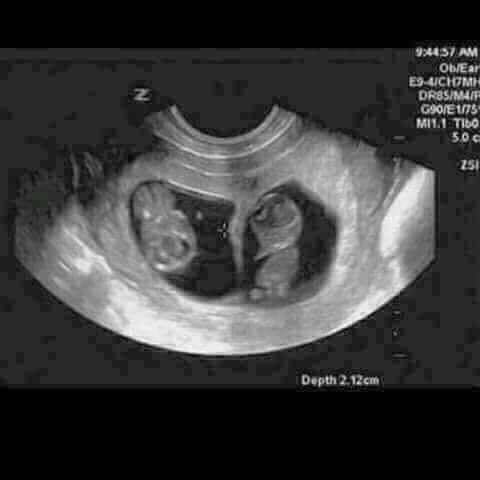

Adelina Pestriţu a pus ecografia pe Facebook! Sunt gemeni!

Mai exact, ea a făcut publică o ecografie în care apar doi bebeluşi, în dreptul căreia a scris: ”WOW... Se pare că 2018 o să fie un an interesant. Cei doi sunt în burtică de 10 săptămâni deja, iar eu habar n-am avut până acum. În ciuda şocului iniţial, cu siguranţă este o surpriză şi mai ales faptul că sunt doi. Nu ştiu dacă sunt băieţi,fetele, ambele, dar cu siguranţă mami şi tati sunt încântaţi şi abia aşteaptă să vă cunoască.